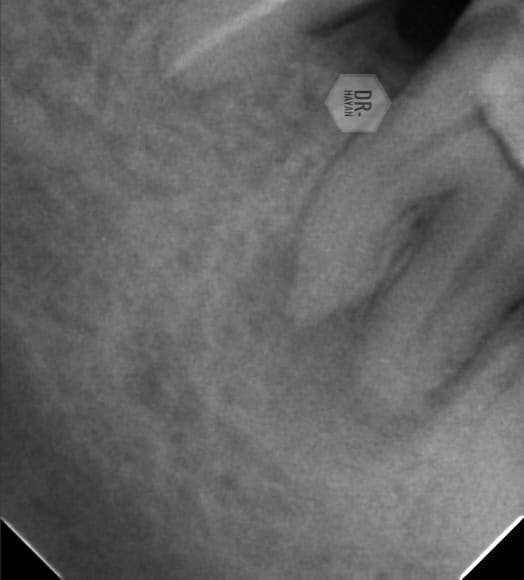

The previous dear doctor can’t located the mb canal , send me this picture

Pre operative X ray